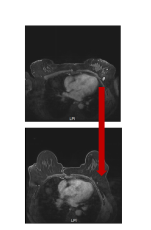

乳房肿块治疗后基本消失

淋巴结退缩至正常范围